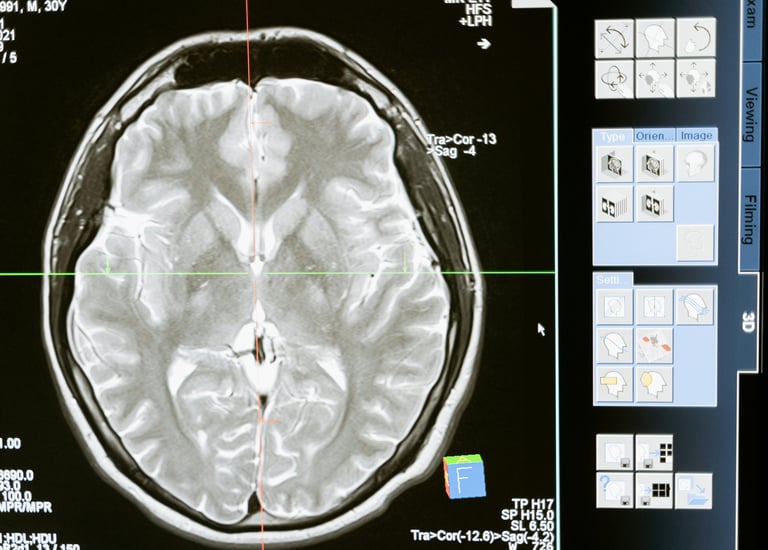

Meningitis

Meningitis is a serious infection that causes inflammation of the membranes surrounding the brain and spinal cord, often leading to symptoms such as fever, headache, and neck stiffness, and requiring urgent medical treatment.